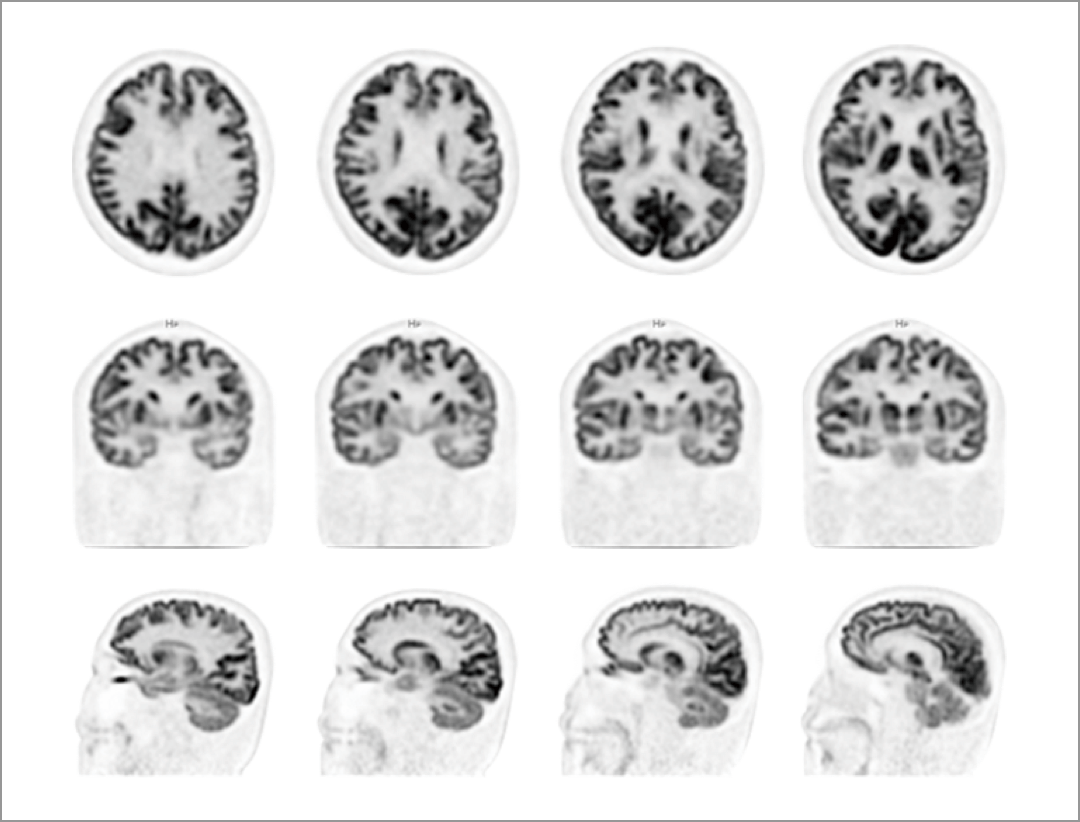

Creier

Imagistica prin PET/CT digital permite vizualizarea detaliată a structurilor cerebrale, fiind esențială în diagnosticul și monitorizarea afecțiunilor neurologice și în detectarea leziunilor de mici dimensiuni.